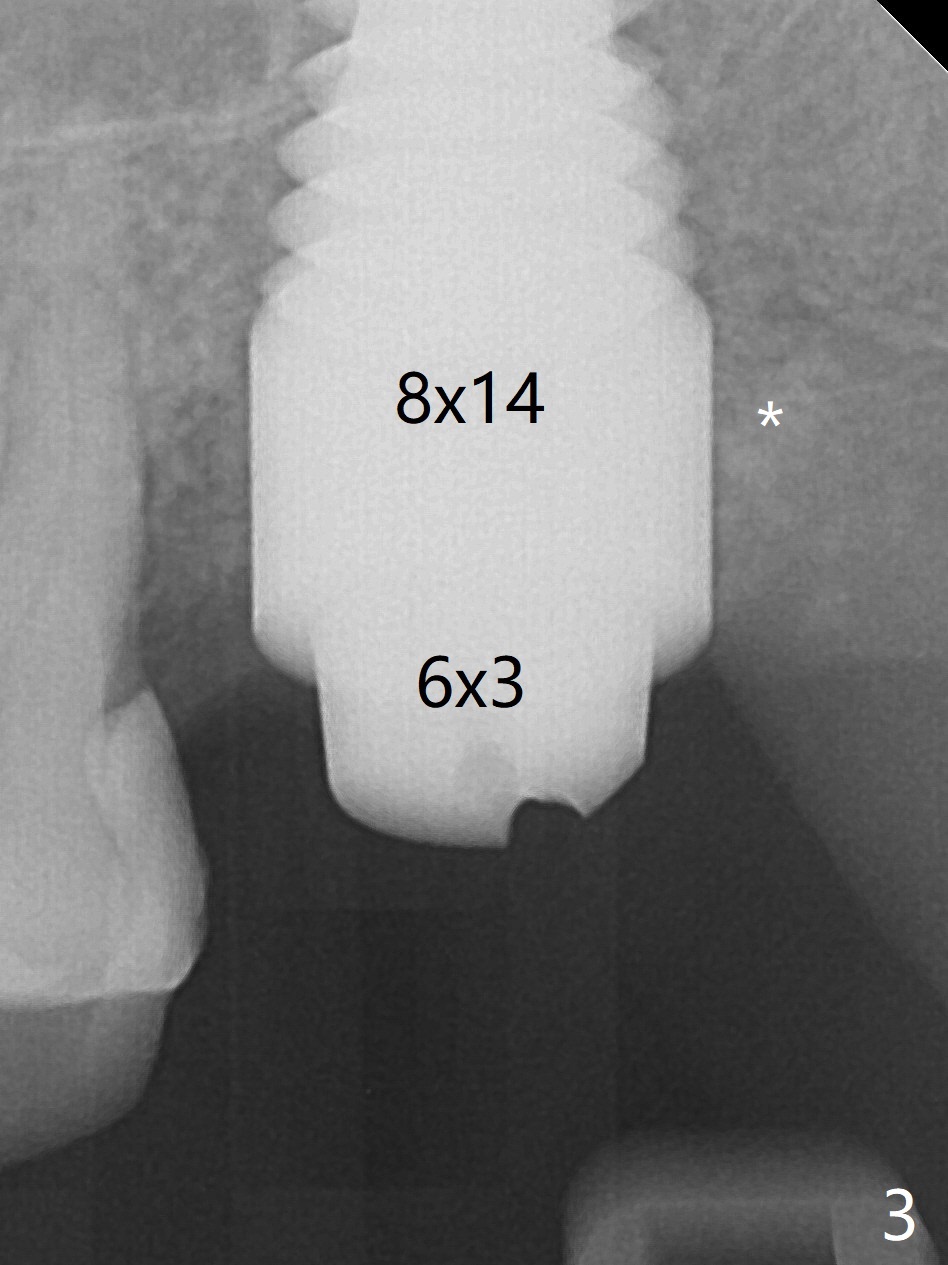

A 56-year-old woman has sign of periimplantitis 2 years 9 months post cementation. After incision, the 5.5x13 mm bone-level implant is ~ 3 mm inferior to the buccal crest. The implant is removed with 7/6 mm trephine bur, elevator and implant driver. The sinus membrane perforates. A 8x17 mm tap achieves stability (Fig.1), but the peripheral bone seems to be thin. Although a 7x14 mm tissue-level implant has stability, it is placed too deep (Fig.2). Following insertion of a piece of Osteogen plug for sinus membrane repair, a 8x14 mm implant is placed with >40 Ncm with allograft placed around the unpolished portion of the implant (Fig.3,4). A 6x3 mm abutment is placed to hold periodontal dressing in place. Because of the abutment with a slot (Fig.5 A), the periodontal dressing remains in place 4 days postop before the patient travels back home for 4 hours. In fact there is no postop sinus infection; the implant threads seems not be exposed 3 months postop (Fig.6). Because of the large implant, it is loaded early (Fig.7, 8 (Temp Bond)). Upper Molar Immediate Implant, Trajectory II 劈开术 Xin Wei, DDS, PhD, MS 1st edition 08/09/2019, last revision 04/11/2021